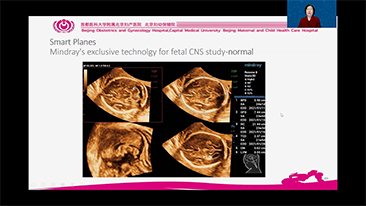

AlimentÊe par la plateforme avancÊe ZST+, la gamme complète de solutions intelligentes Nuewa est con?ue spÊcialement pour amÊliorer la santÊ des femmes avant, pendant et après la grossesse, de manière à poser des diagnostics complets et efficaces pour rÊpondre à des dÊfis cliniques de plus en plus exigeants.